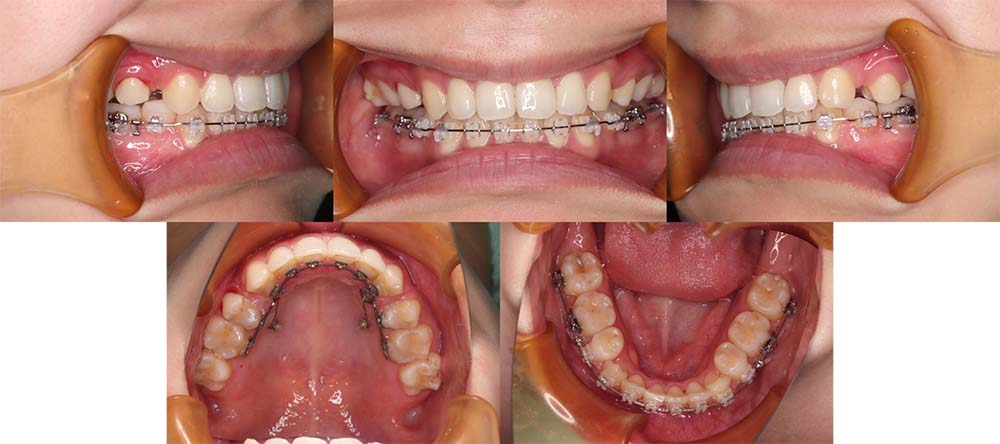

| 症例分類 | 上顎前突、口唇突出 |

| 診断名 | 左下4先天欠損を伴う上下前歯部叢生と骨格性上顎前突 |

| 主訴 | 出っ歯、下の歯がガタガタ、乳歯が1本ある |

| 年齢 | 31歳4ヶ月 |

| 性別 | 女性 |

| 抜歯部位 | 上の左右第一小臼歯と右下第二小臼歯と左下第二乳臼歯(4本) |

| 使用装置 | 上下裏側のワイヤー装置 |

| 治療期間 | 2年9ヶ月 |

| 保定装置 | 固定式保定装置、取り外し式保定装置(8時間) |

| 費用 |

[検査・診断料] ¥49,500 [基本施術料] ¥1,331,000 [調整料] ¥5,500/回 [抜歯] ¥5,500/本 [保定装置] ¥55,000(税込) 抜歯や虫歯治療は他院にて費用が別途かかります。(抜歯¥4,000〜10,000/本)

左下の永久歯が先天欠損で子供の歯が残っていて、その歯が抜けそうになったこともあり、矯正治療を考えて来院されました。

上下叢生と口唇閉鎖不全のため上下の抜歯をして治療をしました。下顎左側乳歯を抜去して治療をしました。

歯の動きが少しゆっくりだったため、予定より治療期間が伸びてしまいましたが問題なく咬合させることができました。